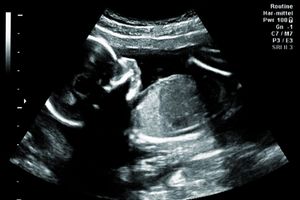

تشخیص بارداری: سونوگرافی یکی از روشهای استاندارد برای تأیید بارداری است. در این روش میتوان سن بارداری، تعداد جنینها، موقعیت جنین و وجود یا عدم وجود مشکلاتی مانند حاملگی خارج از رحم را بررسی کرد.

بررسی رشد و سلامت جنین: سونوگرافی در طول بارداری برای بررسی وضعیت رشد جنین، سلامت قلبی-عروقی آن و بررسی مشکلات احتمالی مانند نقصهای مادرزادی استفاده میشود.